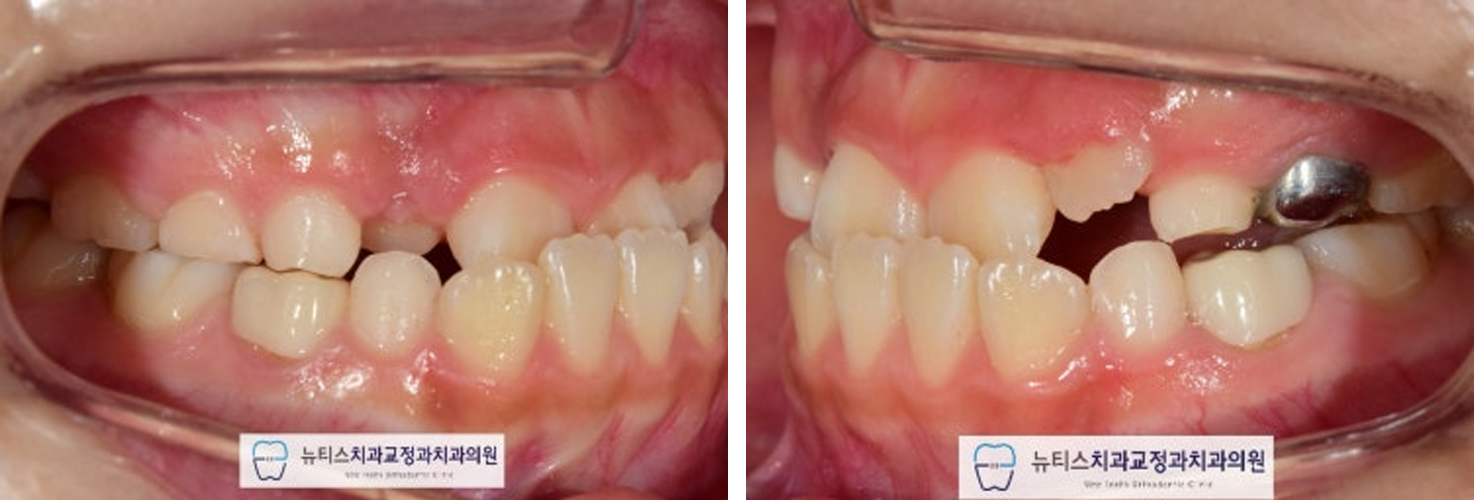

¾È³çÇϼ¼¿ä.ºÎ»ê ±ÝÁ¤±¸ ±¸¼µ¿¿¡ À§Ä¡ÇÑ´ºÆ¼½ºÄ¡°ú±³Á¤°ú Ä¡°úÀÇ¿ø±³Á¤°ú Àü¹®ÀǾȼö¹ü ¿øÀåÀÔ´Ï´Ù. À̹ø ÁÖºÎÅÍ À帶°¡ ½ÃÀ۵ȴٰí ÇÕ´Ï´Ù~Áö³ÁÖ¿¡µµ À帶°¡ ½ÃÀ۵ȴٰí ÇÏ´øµ¥...7¿ùÀº ÈÄ´þÁö±ÙÇÑ ³¯¾¾°¡ À̾îÁö³×¿ä. ÀϱⰡ º¯È¹«»óÇÏ´Ï´Ùµé °Ç° °ü¸® Àß ÇÏ½Ã±æ ¹Ù¶ø´Ï´Ù~ À̹ø¿¡ Æ÷½ºÆÃÇÒ ÄÉÀ̽º´Â"#ºÎ»ê¾î¸°À̹ݴ뱳ÇÕ ÀÔ´Ï´Ù. ¹Ý´ë±³ÇÕÀ» °¡Áö°í ÀÖÀ¸¸é Á¤»óÀûÀÎ ¼ºÀå ¹ßÀ°À» ÇÏÁö ¸øÇÏ¿©ÁÖ°ÆÅÎÀÌ ´õ ½ÉÇØÁú ¼ö ÀÖÀ¸¸ç ºÎÁ¤±³ÇÕÀÌ ¹ß»ýµË´Ï´Ù. ¼ºÀÎÀÇ °æ¿ì ½ÉÇÑ ¹Ý´ë±³ÇÕ Áï, ÁÖ°ÆÅÎÀº ±³Á¤Ä¡·á¸¸À¸·Î ÇØ°áÀÌ ¾î·Á¿ï ¼ö ÀÖÀ¸³ª ¼ºÀå±â ¾î¸°ÀÌÀÇ °æ¿ì¿¡´ÂÁ¤»óÀûÀÎ ¼ºÀå ¹æÇâÀ¸·Î À¯µµÇØ º¼ ¼ö ÀÖ½À´Ï´Ù. À̰¡ Ʋ¾îÁö°í µ¡´Ï°¡ Àְųª °ø°£ÀÌ ¸¹ÀÌ ÀÖ´Â °æ¿ì¿¡´Âº¸È£Àںв²¼ ÀÎÁö°¡ ºü¸£³ªÀÌ·± ºÎÁ¤±³ÇÕ (¹Ý´ë±³ÇÕ) À» °¡Áö°í ÀÖÀ¸¸é Àß ¸ð¸£½Ã´Â °æ¿ì°¡ ¸¹½À´Ï´Ù. ÈçÈ÷ ¾Þ±Û¾¾ 3±Þ ºÎÁ¤±³ÇÕÀ̶ó°í Çϴµ¥À̸¦ ¹æÄ¡ÇÏ°Ô µÇ¸é ³ªÁß¿¡ ¹®Á¦°¡ Å©°Ô µÉ ¼ö ÀÖÀ¸´Ï°¡±ÞÀû ºü¸¥ Á¢±ÙÀÌ ¿ä±¸µË´Ï´Ù.(¾ÆÀÌ º¸Çè¿¡¼ º¸ÀåÇØ ÁÖ´Â °æ¿ìµµ ÀÖ½À´Ï´Ù) #ºÎ»ê¾î¸°À̱³Á¤Ä¡°ú ÀÎ ÀúÈñ ´ºÆ¼½º¿¡¼´Â¼ö¿ÏºÎ (¼Õ»À) ¿¢½º·¹À̸¦ ÅëÇØ¿ì¸® ¾ÆÀÌÀÇ ¼ºÀå ´Ü°è¸¦ ÆÇ´ÜÇÏ¿© °¡Àå ÀûÀýÇÑ ½Ã±â¿¡ Ä¡·á¸¦ ÁøÇàÇÒ ¼ö ÀÖµµ·Ï ÇØ µå¸³´Ï´Ù. À̰¡ ¹Ý´ë·Î ¹°¸°´Ù°í ÇÏ¿©#ºÎ»ê¾î¸°À̱³Á¤Ä¡°ú ÀÎ ÀúÈñ ´ºÆ¼½º·Î³»¿øÇϽŠºÐÀÔ´Ï´Ù.ÃÊÁø »çÁøÀÔ´Ï´Ù.È¥ÇÕÄ¡¿±â ´Ü°è·Î ÇöÀç ¾Õ´Ï°¡ ¹Ý´ë·Î ¹°¸®°í ÀÖ½À´Ï´Ù. ÀÌ·¯ÇÑ #ºÎ»ê¾î¸°À̹ݴ뱳ÇÕ À» º¸ÀÌ´Â °æ¿ì¿¡´ÂÁ¤»óÀûÀÎ ÅÎÀÇ ¼ºÀåÀ» ÀúÇØÇÒ ¼ö ÀÖ½À´Ï´Ù. ¹æ»ç¼± »çÁø¿¡¼µµ¾Õ´ÏÀÇ ¹Ý´ë±³ÇÕÀ» È®ÀÎÇÒ ¼ö ÀÖ½À´Ï´Ù. #ºÎ»ê¾î¸°À̱³Á¤Ä¡°ú ÀÎ ÀúÈñ ´ºÆ¼½º¿¡¼´Â¿©·¯°¡Áö °Ë»ç¸¦ ÅëÇÏ¿© ÇÁ¸®¿Ã¼Ò¶ó´Â ÀåÄ¡¸¦ »ç¿ëÇÏ¿©#ºÎ»ê¾î¸°À̹ݴ뱳ÇÕ À» °³¼±Çϱâ·Î ÇÏ¿´½À´Ï´Ù.  Ä¡·á ÈÄ »çÁøÀÔ´Ï´Ù.

#ºÎ»ê¾î¸°À̹ݴ뱳ÇÕ ÀÌ °³¼±µÇ¾ú°íÀüÄ¡ºÎÀÇ ±³ÇÕ°ü°è°¡ ¾çÈ£ÇØ Á³½À´Ï´Ù. Ä¡·á ÈÄ ¹æ»ç¼± »çÁø¿¡¼µµ¹Ý´ë±³ÇÕÀÌ °³¼±µÈ °ÍÀ¸·Î È®ÀÎÇÒ ¼ö ÀÖ½À´Ï´Ù.(Ä¡·á±â°£ 6°³¿ù)  Ä¡·á Á¾·á ÈÄ 1³â Áö³ »çÁøÀÔ´Ï´Ù. #ºÎ»ê¾î¸°À̱³Á¤Ä¡°ú ÀÎ ÀúÈñ ´ºÆ¼½º¿¡¼´Â¹Ý´ë±³ÇÕÀ» °³¼±ÇÑ ÀÌÈÄ, À¯Áö°¡ Àß µÇ´ÂÁö ´Ù¸¥ ¹®Á¦°¡ ¾ø´ÂÁö ÁÖ±âÀûÀΠüũ¸¦ ½ÃÇàÇÕ´Ï´Ù. ÃÊÁø, Ä¡·á ¸¶¹«¸®, 1³â À¯Áö üũ »çÁøÀÔ´Ï´Ù. Àß À¯Áö°¡ µÇ¾ú°í ÀûÀýÇÑ ½Ã±â°¡ µÇ¸é2Â÷ ±³Á¤À» ÁøÇàÇÒ ¿¹Á¤ÀÔ´Ï´Ù~ #ºÎ»ê¾î¸°À̹ݴ뱳ÇÕ ÀÇ °æ¿ì¿¡´ÂÄ¡·áÀÇ Å¸À̹ÖÀÌ Áß¿äÇϱ⠶§¹®¿¡ Àü¹®°¡¿Í »ó´ãÇÏ´Â °ÍÀÌ Áß¿äÇÕ´Ï´Ù. #ºÎ»ê¾î¸°À̱³Á¤Ä¡°ú ÀÎ ÀúÈñ ´ºÆ¼½º¿¡¼´Â¿ì¸® ¾ÆÀÌ¿¡ ´ëÇÏ¿© ´Ù¾çÇÑ °Ë»ç¸¦ ÅëÇØÃÖÀûÀÇ Ä¡·á ¹æ¹ýÀ» µµ¸ðÇØ µå¸®°í ÀÖ½À´Ï´Ù. Ȥ½Ã ¿ì¸® ¾ÆÀÌÀÇ Ä¡¾Æ°¡ ¹Ý´ë·Î ¹°¸°´Ù´øÁö¾ÕÀ¸·Î »ÀÃÄÁ³´Ù¸é ¾ðÁ¦µçÁö ¸Á¼³ÀÌÁö ¸¶½Ã°íÀúÈñ ´ºÆ¼½º·Î ¿¬¶ô ÁÖ¼¼¿ä~